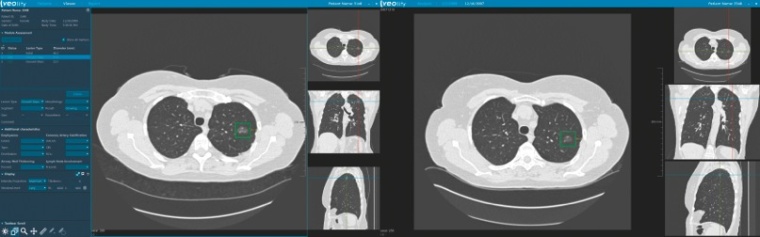

Mit Veolity bietet der Spezialist für Medizinsoftware MeVis Medical Solutions AG in Bremen/Deutschland eine dedizierte Befundstation für das CT-Lungenkrebs-Screening an. Basierend auf aktuellen Forschungsergebnissen optimiert Veolity den Arbeitsablauf und kombiniert die FDA-zugelassene automatische Lungenrundherderkennung (CAD - computer-aided detection) mit der automatischen Registrierung von Voraufnahmen und effizienter Befunderstellung. Die Befunde werden automatisiert nach aktuellen Standards und Richtlinien er-stellt - inklusive einem aktuellen Modell zur Vorhersage der Bösartigkeit. Automatische Messungen, Integration von Nebenbefunden, Bestimmung des Patientenmanagements und die Einbindung von Screeninglisten machen das System zu einer Komplettlösung für die Befundung von Lungenkrebs-Screening-CTs.

"CT-Lungenkrebs-Screening für Hochrisikogruppen wird jedes Jahr tausende Leben retten. Wir begrüßen die Entscheidung der CMS, nicht nur weil sie das Interesse an unseren Produkten fördert, sondern vor allem aufgrund des enormen Nutzens für die Patienten.", erklärt Bernd Kümmerlen, Produktmanager, MeVis Medical Solutions AG. "Mit Veolity versuchen wir die Arbeit für den Radiologen leichter zu machen, während wir gleichzeitig die Qualität verbessern und damit den Patientennutzen erhöhen. Lungenrundherde zu finden, zu vermessen und mit Voraufnahmen zu vergleichen, ist eine mühsame Arbeit. Veolity automatisiert viele dieser Schritte und ermöglicht Präzision in der Diagnostik durch die Rundherderkennung, durch objektive Messwerte und die Vergleichsfunktion zu Voraufnahmen."